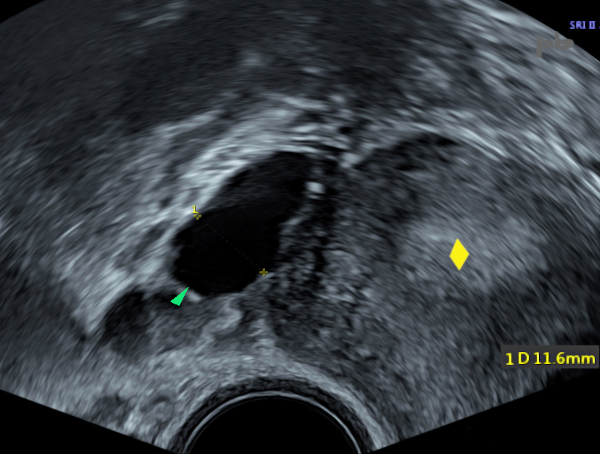

8 – Hydrosalpinx

(même patiente que 7)

Echographie-doppler.

Apparition d’un hydrosalpinx droit avec une lumière tubaire irrégulière (►) lors d’une stimulation ovarienne. La paroi est épaissie (★), séquelle d’un processus inflammatoire.

Pas de flux enregistrable.

8 – Hydrosalpinx

(Same patient as case 7)

Ultrasound-Doppler. Appearance of a right hydrosalpinx with an irregular tubular lumen (►) during ovarian stimulation. The wall is thickened (★), a sequela of an inflammatory process. No detectable blood flow.